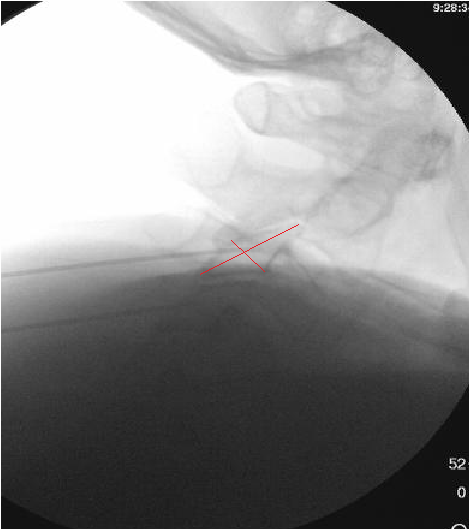

Only thing I do differently is aim for a touch more posterior placement of the needle. I try to make sure the very tip of the needle is at but not beyond the x in the image below. I also take a final lateral right before RFA. I think it helps reduce the frequency of neuritis to be a bit more posterior.

View attachment 395708

I appreciate the input, but I'm using a 10mm active tip and I'm burning quite a bit of MBN in that pic right there. Going more posterior theoretically means I'm getting less of it.

I think there is a very substantial cutaneous aspect to these nerves.

Based on some discussion on here a few years back, I tried burning 1/2 way along the pillar rather than anterior edge, but felt like I saw an immediate increase in neuritis. I suspect there are at least 2 different causes. Some neuritis comes from burning nerves with a sensory input to the skin, unavoidable, but some comes from being a little off target and only irritating rather than completely burning a medial branch nerve.